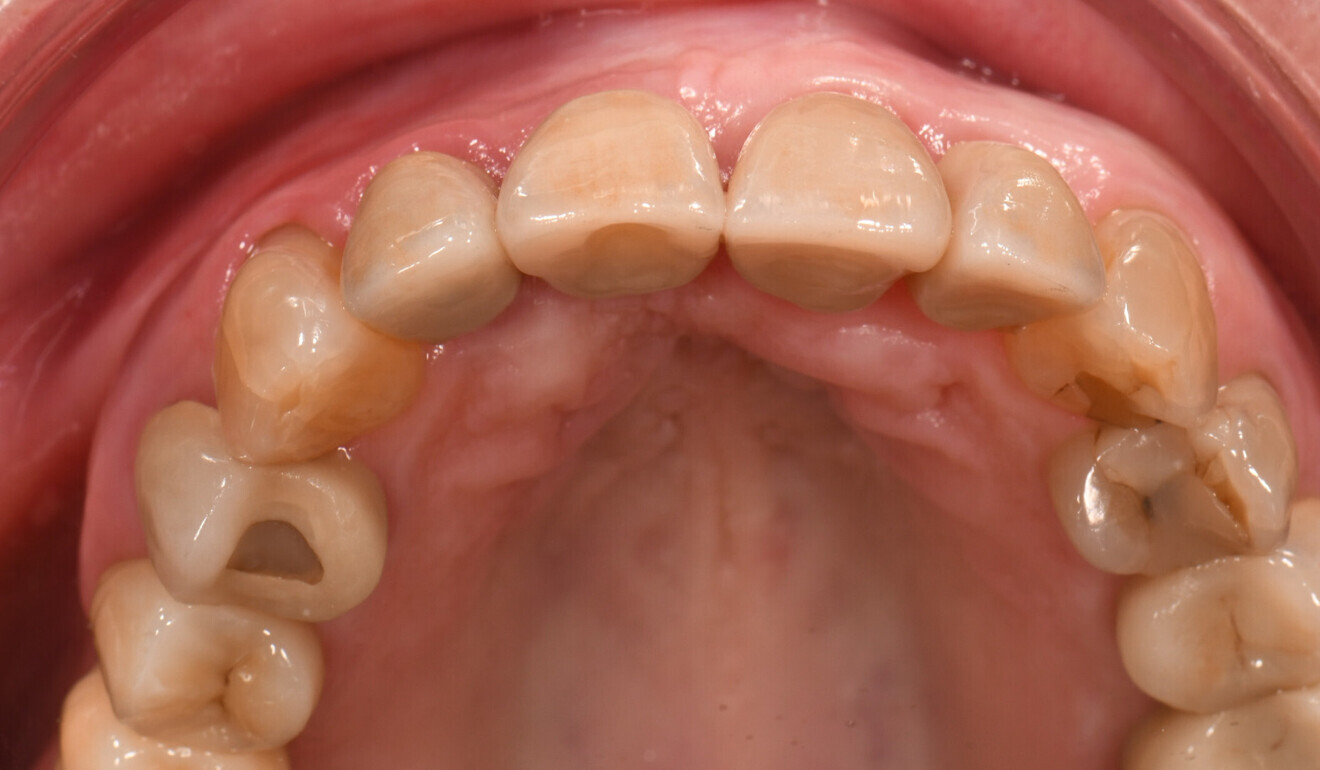

Fig. 2: Initial situation, occlusal view of the maxilla.